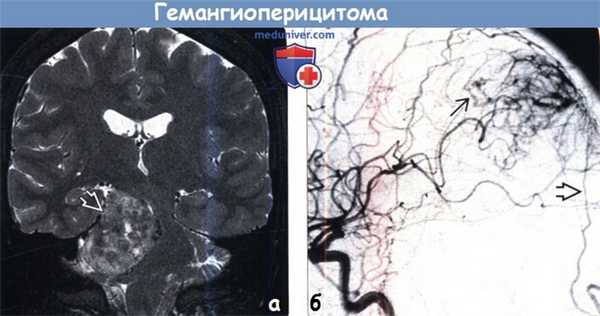

(а) МРТ, Т2-ВИ, режим подавления сигнала от жира, корональный срез: определяется крупное гетерогенное объемное образование, сконцентрированное в правом мостомозжечковом углу и имеющее связь с твердой мозговой оболочкой. При резекции была диагностирована гемангиоперицитома.

(б) ЦСА, контрастирование ВСА, боковая проекция: определяется артериовенозное шунтирование с ранним венозным дренированием. Также наблюдается дополнительный питающий сосуд — ветвь затылочной артерии. Для гемангиоперицитом характерно смешанное кровоснабжение из сосудов твердой и мягкой мозговых оболочек. Часто полезно проведение предоперационной эмболизации.

3. МРТ при гемангиоперицитоме (ГПЦ):

• Т1-ВИ:

о Объемное образование гетерогенной структуры, изоинтенсивное по отношению к серому веществу

о Могут наблюдаться участки потери сигнала за счет эффекта потока

• Т2-ВИ:

о Гетерогенное изоинтенсивное объемное образование

о Часто наблюдаются выраженные участки потери сигнала за счет эффекта потока

о Характерны перифокальный отек, масс-эффект

о Может наблюдаться гидроцефалия

• Постконтрастное Т1-ВИ:

о Интенсивный, часто гетерогенный характер накопления контраста

о Дуральный «хвост» в 50% случаев о Может наблюдаться область центрального некроза

• МР-венография:

о Может наблюдаться окклюзия синусов твердой мозговой оболочки

4. Ангиография:

• Гиперваскулярное объемное образование с неравномерно выраженными кровоснабжающими опухоль сосудами и пролонгированным контрастированием опухоли по типу «пятна»

• Обширное артериовенозное шунтирование

• Характерно смешанное сосудистое кровоснабжение из твердой и мягкой мозговых оболочек

• Полезна предоперационная эмболизация